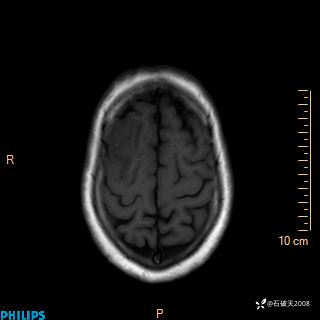

2020.11.14MR

T1